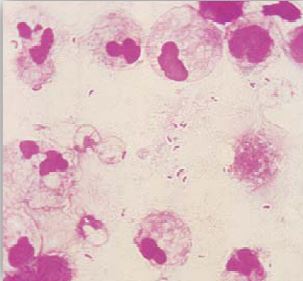

صبغة جرام لعينة سائل النخاع الشوكي توضح الخلايا البكتيرية المحاطة بالحافظة.